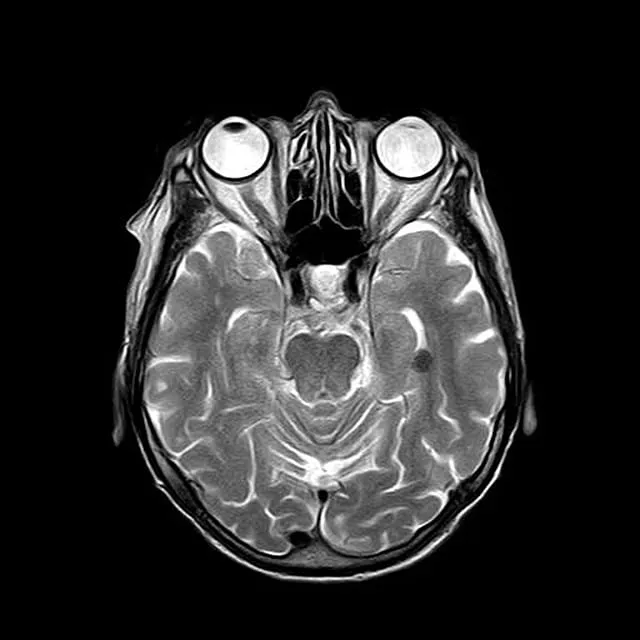

영상 검사

필요한 경우 MRI나 CT 스캔과 같은 영상 검사를 통해 두개 내 구조적 문제를 확인할 수 있습니다. 이러한 검사는 특히 신경학적 증상이 동반될 때 중요합니다.